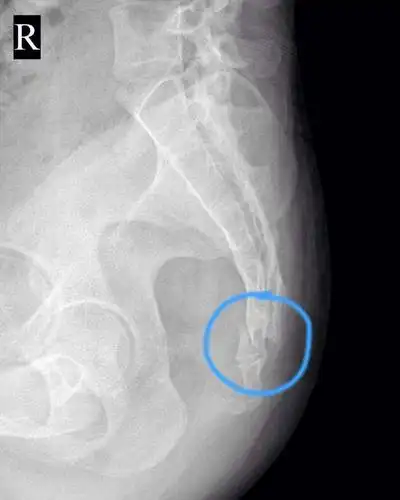

55岁不幸患尾骨骨折,花费近六千元骶尾部疼痛好转

骶尾骨骨折后生小孩能顺产吗?如要不能还能正过来吗?